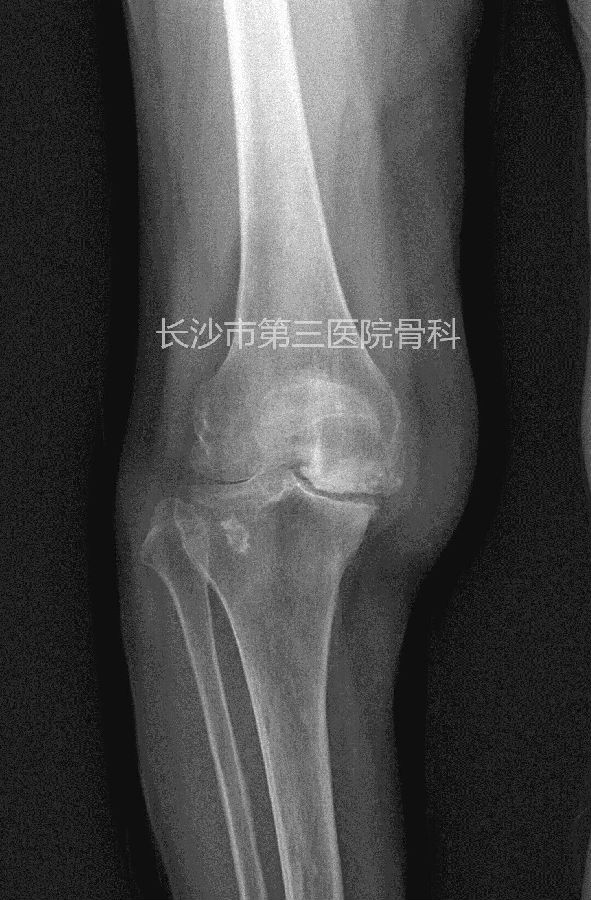

患者李某,女性,76岁。因反复右膝肿痛、活动受限10年,加重4天入院。体查:右膝内翻畸形,屈90度,伸10度,内侧关节间隙及髌骨上缘压痛,侧方应力试验阴性,肌力正常。诊断“右膝骨性关节炎”,为人工全膝关节置换适应症。

术前平片: